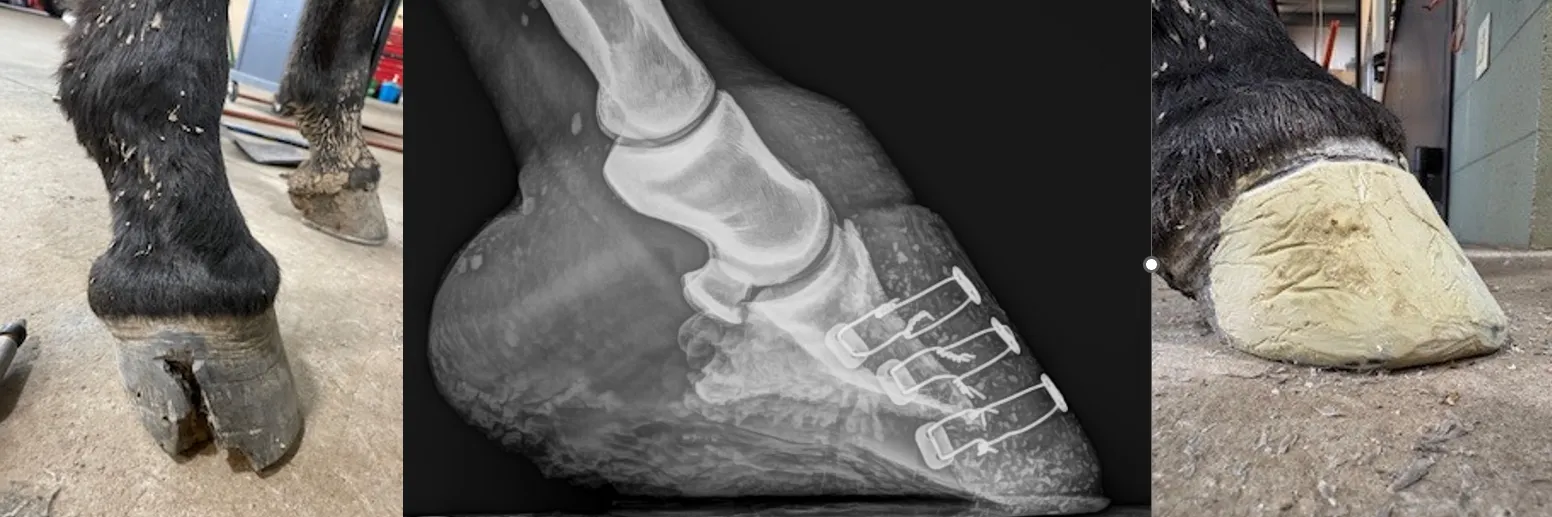

Here is a couple picts of a recent unattended seedy toe which resulted in osteomyelitis of the coffin bone from start to finish.  Check out the full story and video on our facebook and instram pages.

seedy toe repair

finished product (N Oetter)